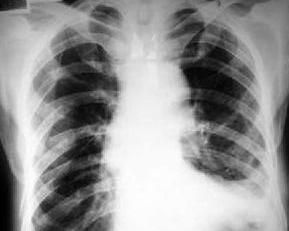

X線胸片上大都能夠顯示肋骨骨折,但對於肋軟骨骨折,“柳枝骨折”,骨折無錯位,或肋骨中段骨折在胸片上因兩側的肋骨相互重疊處,均不易發現,應行CT等進一步檢查並結合臨床表現來判斷以免漏診。

肋骨骨折的診斷主要依據受傷史,臨床表現和X線胸片檢查。如有胸部外傷史,胸壁有局部疼痛和壓痛,胸廓擠壓試驗陽性,應想到胸廓骨折可能,結合X線檢查可確診,如果壓痛點可觸到摩擦音,診斷可確立,如果胸壁出現反常呼吸運動,說明有多根多處肋骨骨折。